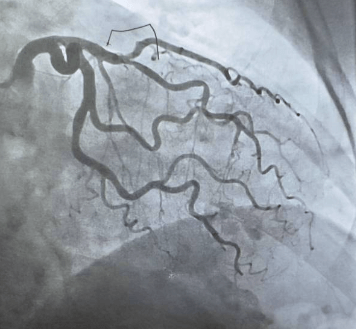

협심증(Angina Pectoris)은 심장 근육에 산소와 영양을 공급하는 관상동맥이 일시적으로 좁아지면서 심장에 혈액 공급이 부족해지는 증상입니다. 이로 인해 가슴에 통증이나 압박감이 발생하게 됩니다.

이는 일종의경고신호로 볼 수 있으며, 심근경색으로 진행되기 전에 나타나는 심장 질환의 전단계일 수 있습니다. 협심증은 주로 운동이나 스트레스 상황에서 심장이 더 많은 혈액을 요구할 때 증상이 나타나며, 휴식을 취하면 증상이 사라지는 것이 특징입니다.